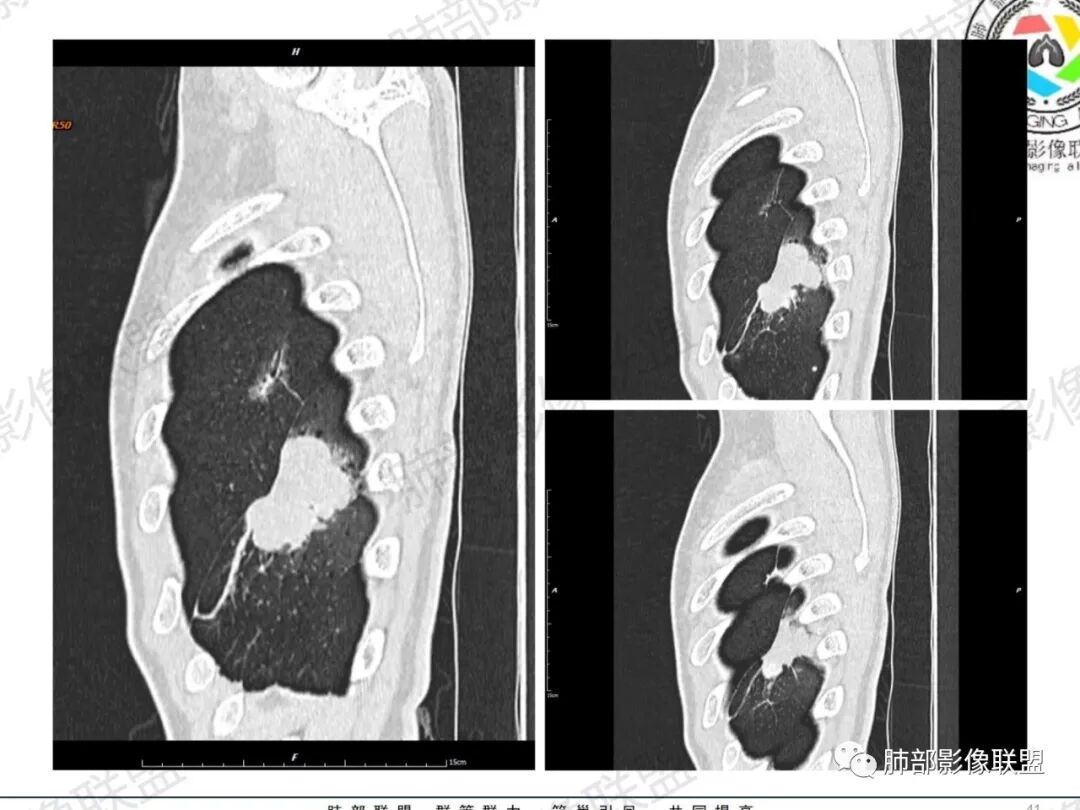

一切∮随缘:左肺下叶不规则肿块,边缘光滑,平直,局部彭隆,分叶,近端支气管堵塞,远端与胸膜相贴,平扫密度尚均匀,增强后不均匀强化,内部可见低密度坏死,胸膜下多发肺气肿,伴双肺散在光滑小结节,实验室肿瘤标志物高,考虑恶性:神经内分泌癌(大细胞),腺癌,鳞癌。

琦遇:恶性没有问题,肺气肿底子、病灶分叶、少许毛刺、叶间胸膜凹陷、部分边缘可见清晰的GGO、胸膜牵拉凹陷、局部胸水、近端支气管截断、部分支气管被推移、占位效应明显、强化特点为不均匀强化、内部有少许沼泽样低强化区,强化部分轻中强化为主、余肺可见转移性结节、左肺上叶似为囊腔型腺癌一枚,肿瘤标志物提示非小、神经内分泌,综合分析考虑大神泌、腺癌、腺鳞癌、鳞癌  同时左肺上叶囊腔型腺癌  肺转移

蕊:中老年男性,吸烟史,肺气肿背景,左肺上叶类圆形肿块影,边界清晰,边缘凹凸不平,有分叶,支气管进入阻断,临近胸膜栽赃,整体病灶膨隆,局部周围可以清晰ggo,临近叶间裂内凹,轻度强化,并可见多个低密度区,坏死可能,界线不清;肺内多结节,边缘光滑,考虑恶性伴转移,鳞癌、腺癌

傅昌瑜:中老年男性,肺气肿背景,右胸背疼痛1周。CEA、NSE、CYFRA—211升高。左上肺混合磨玻璃结节,内见较多空泡和扩张支气管。左下肺胸膜下肿块,边缘较光滑,深分叶,似有血管进入,与支气管关系不清,内见不均匀强化,见沼泽地样坏死,有胸膜栽赃。另两肺多发圆形小结节。考虑恶性并肺内转移,多原发可能性大,左上肺腺癌,左下肺病理难以判断,小细胞癌?鳞癌?

蓝天白云:中年男性,肺气肿背景,左肺下叶肿块,边缘膨隆,有分叶,内有湖泊样坏死,有轻中度强化,局部胸膜栽赃,收缩力不强,周围见肺气肿征象。左肺上叶混合磨玻璃影,边界清楚,考虑都是恶性,左上肺iac,左下肺腺鳞癌,或大细胞肺癌可能。两肺多发结节,考虑转移

LCNEC最常见的影像特征包括:(1)肿块发生部位:周围型肺癌为主,少数发生于肺中央。(2)肿块大小及形态。因肿瘤细胞生长迅速常形成较大肿块,因此其体积一般较大,直径常在3~10cm范围内,病灶常为不规则形软组织肿块。(3)肿块边界。多数学者报道大多数肿块边界清晰,边缘呈分叶状,毛刺征及“胸膜凹陷征”少见,认为与该病对周围组织浸润较轻及较少产生纤维瘢痕组织牵拉有关联。(4)肿块密度、强化特点及代谢情况。据文献报道,该类肿瘤因体积较大CT上常见软组织肿块,且多数密度不均匀,内见囊变坏死区,增强后呈轻或中度不均匀强化(可见强化者占75.7%),认为其强化特点与其内部肉眼可见坏死灶和肿瘤较大直径有关。(5)伴随症状及远处转移。该病恶性程度高,侵袭性强,常侵犯邻近结构,如胸膜、心包、邻近骨质或纵隔内组织等,易出现纵隔淋巴结转移,部分发生肺内及远处转移,少数早期可出现广泛远处转移。